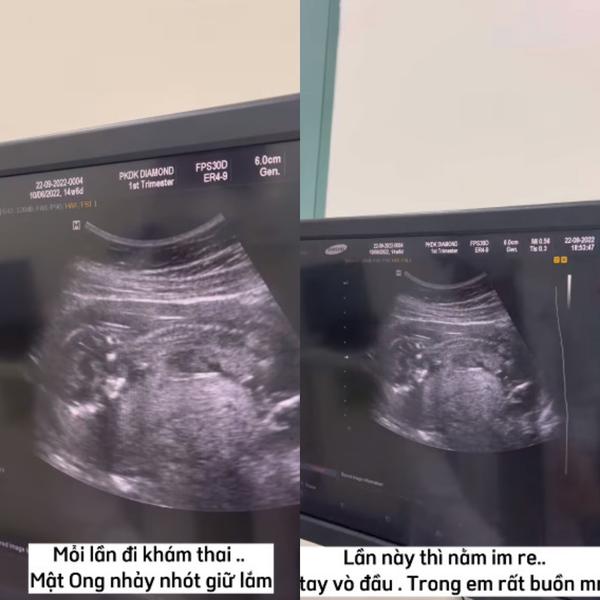

“Mỗi lần đi khám thai, Mật Ong (tên em bé trong bụng - PV) nhảy nhót dữ lắm. Lần này thì nằm im re, lấy tay vò đầu, trông rất buồn mọi người ạ.